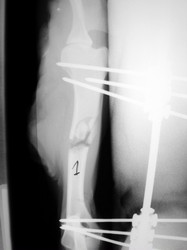

PRÁCTICAS CURSO DE FIJACIÓN EXTERNA PERFECCIONAMIENTO.

Húmero.